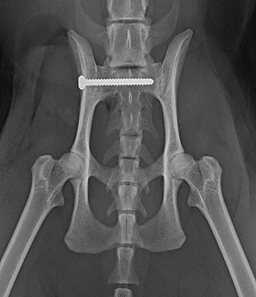

Beispiele aus der Orthopädie

- Frakturoperationen

- Symphysiodese bei Welpen

- Beckenosteotomie (DPO/TPO)

- Patellaluxation